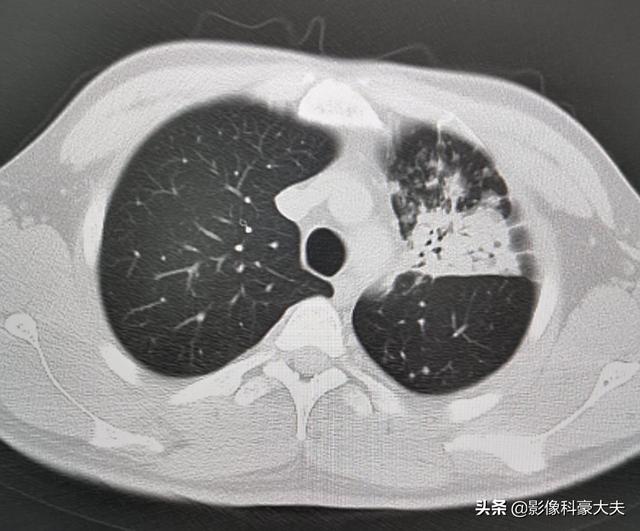

この患者は30歳を過ぎたばかりで、血糖値は20を超えていた。結核の二次感染で、左側の肺組織が大規模に破壊され、大きな空洞が多数形成され、血を吐いていた。

免疫機能が低下した糖尿病患者は、黄色ブドウ球菌、アスペルギルス、結核菌、肺炎桿菌などの感染症にかかりやすい。

このチャップはOKで、1年間計画的に治療した結果、病巣はかなり吸収された。